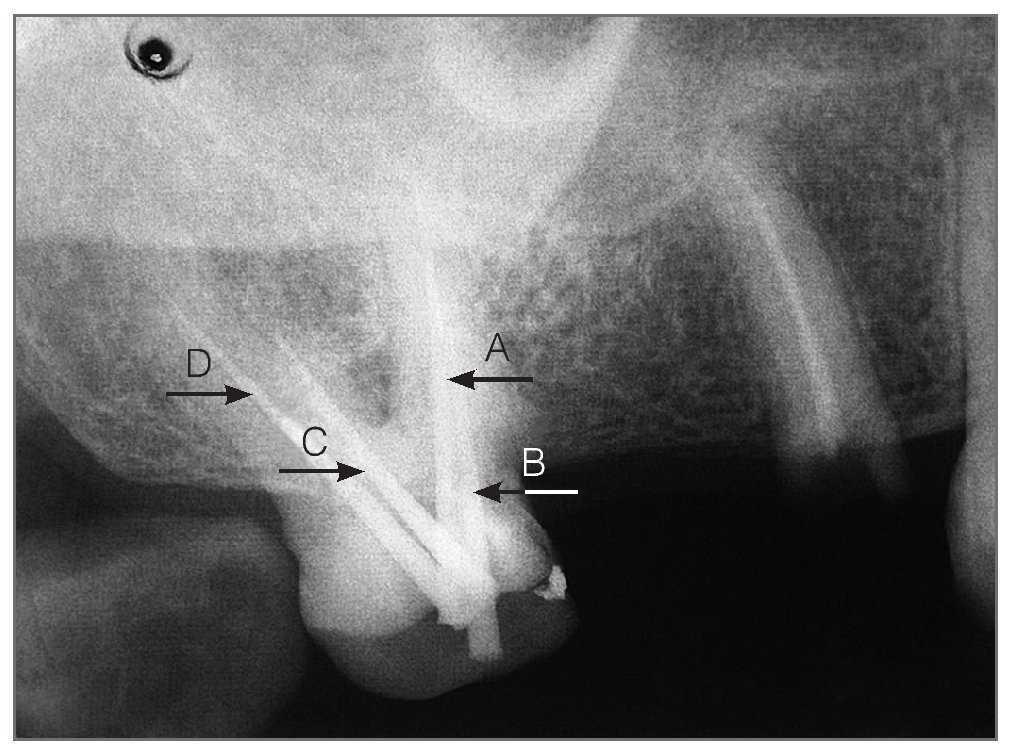

Figura 4a. Ajuste de las 4 puntas de gutapercha. (A) vestibulomesial; (B) palatino accesorio; (C) vestibulodistal; (D) palatino principal.

Figura 4b. Obturación de los 4 conductos radiculares con gutapercha. (A) vestibulomesial; (B) palatino accesorio; (C) vestibulodistal; (D) palatino principal.